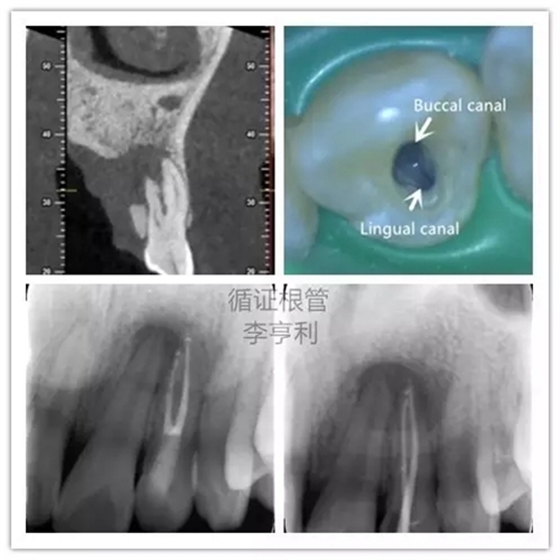

5,根管解剖的評估

上頜側(cè)切牙擁有雙根管

在CBCT的掃描中,根管形態(tài)能在三維的條件下評估,能準(zhǔn)確顯示根管數(shù)量和多個(gè)根管之間的聯(lián)系。根據(jù)Matherne et al. (2008)的間接體外研究(ex vivo),牙體牙髓??漆t(yī)生單憑閱讀數(shù)碼X片,即使一個(gè)牙齒進(jìn)行多個(gè)角度拍攝,還是有40%的樣本牙齒出現(xiàn)至少一個(gè)遺漏根管。

對于最容易被疏忽的上頜磨牙MB2根管,CBCT正確判斷其是否存在的幾率高達(dá)79%,與金標(biāo)準(zhǔn)的牙齒切片(sectioning)準(zhǔn)確率無統(tǒng)計(jì)學(xué)上的區(qū)別(Blattner et al. 2010)。所以,即使對于非手術(shù)性的根管再治療(non-surgical retreatment),CBCT也能提供巨大的治療價(jià)值。